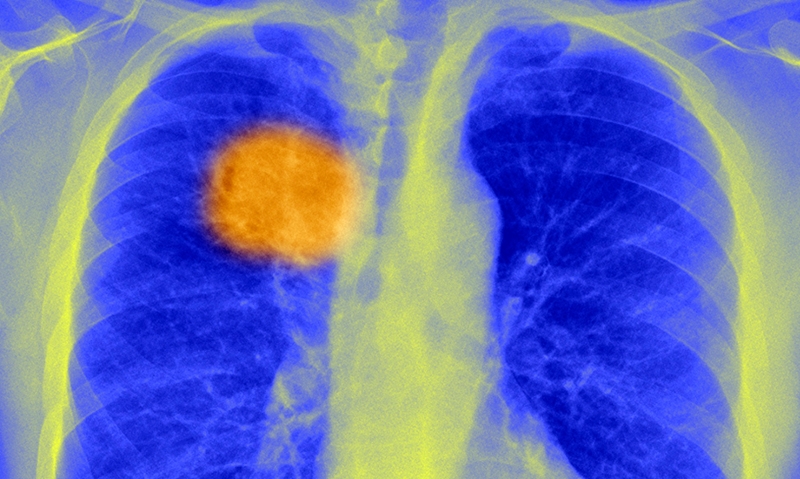

EXPERTS fear Australians are dying of lung cancers which could have been successfully removed, as new research reveals wide variation in resection rates between health districts.

The study, published in the MJA, included 3040 NSW patients diagnosed with localised (stage 1A and 1B) non-small cell lung cancer (NSCLC) between 2003 and 2007. It found resection was associated with a 70% reduction in deaths 5 years after diagnosis. (1)

However, a postcode lottery was apparent in the management of such patients, with one local health district performing resections in 59% of patients, compared with a state average of 38%‒43%.

They concluded that deaths from all NSCLC at 5 years after diagnosis “would be reduced by about 10%” if all local health districts achieved a resection rate of 59%. Localised cases comprised 30% of all NSCLC cases of known stage in NSW.